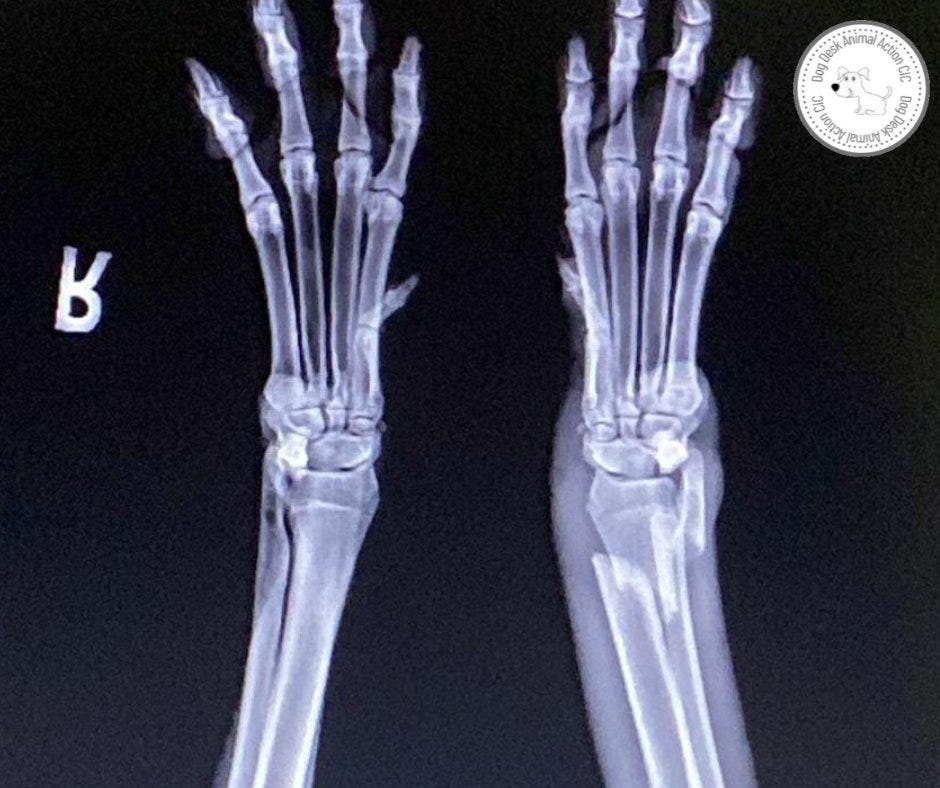

Tara suffered from a compound fracture, where the bone was protruding through her leg after piercing the skin.

This type of fracture poses a higher risk since infections can easily penetrate the skin and start causing harm. It was crucial for her to undergo urgent surgery as soon as possible.

Dr. S, our remarkable orthopedic surgeon, skillfully placed a plate in Tara's leg to aid in the healing of her bones. There was a moment of intense urgency among the vets as they searched for a plate large enough for the procedure.